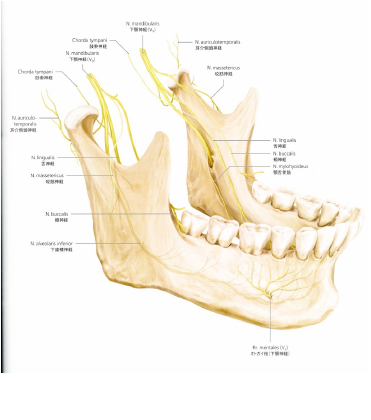

当院では「親知らず」の抜歯においてCT装置によるエックス線画像診断を行いベストな術式の選択を行っております。

以下は「親知らず」の抜歯において神経損傷のリスクを回避する処置を行い安全・安心な抜歯を行った症例です。

※下あごの「親知らず」が血管・神経と重なる場合抜歯による神経損傷は3~5%の確率で発生すると言われています。

「親知らず」を神経から引き離す処置をしました。

神経損傷のリスクを回避するためです。